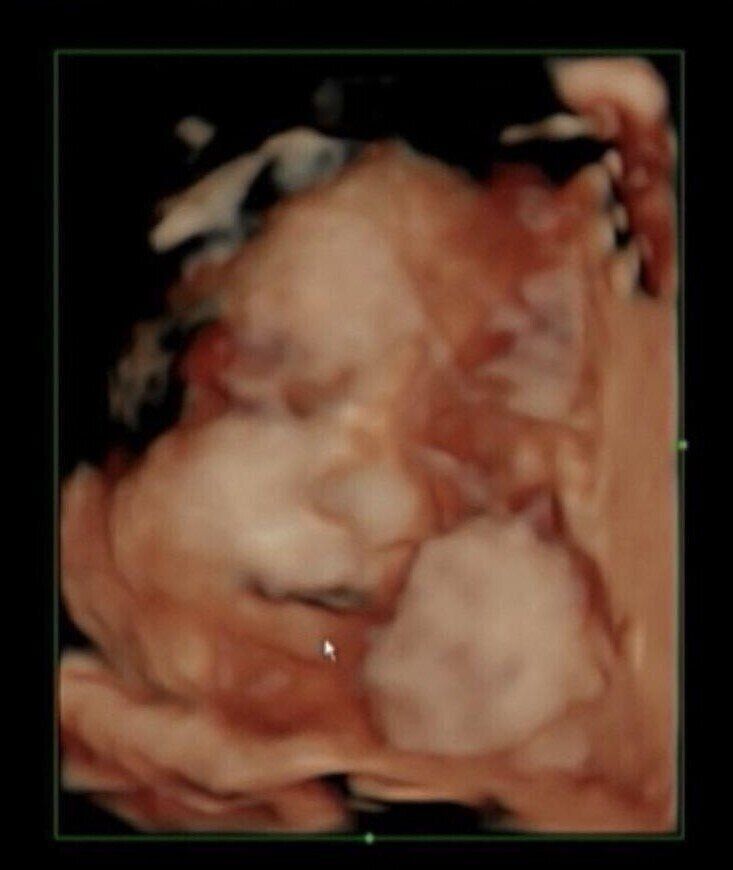

無痛分娩、予定日超過レポ